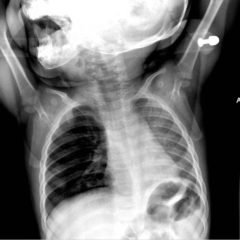

The chest X-ray demonstrated a markedly widened mediastinum (red brackets), raising concern for thoracic aortic aneurysm/aortic dissection, which prompted labs and contrast-enhanced computed tomography (CT) of the chest. The CT revealed a dilated proximal esophagus that narrowed distally (yellow tracing and red arrow), with particulate material, mass-effect on the trachea (purple outline), and bilateral patchy opacities suggesting aspiration. Barium esophagram showed a drastically dilated esophagus filled with contrast (yellow arrow), terminating into the classic “bird’s beak sign” (red arrow) at the lower esophageal sphincter (LES). Esophageal manometry later confirmed achalasia, proving that widened mediastina can have unexpected etiologies.